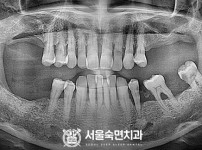

임플란트-전후사진2